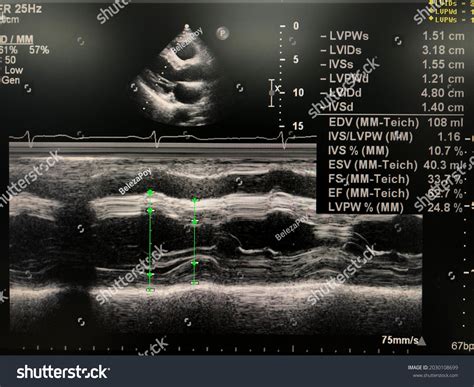

• Echocardiogram: This is the most common test. It uses ultrasound waves to create real-time images of the heart, allowing the technician to measure the chamber volumes at the beginning and end of a contraction.